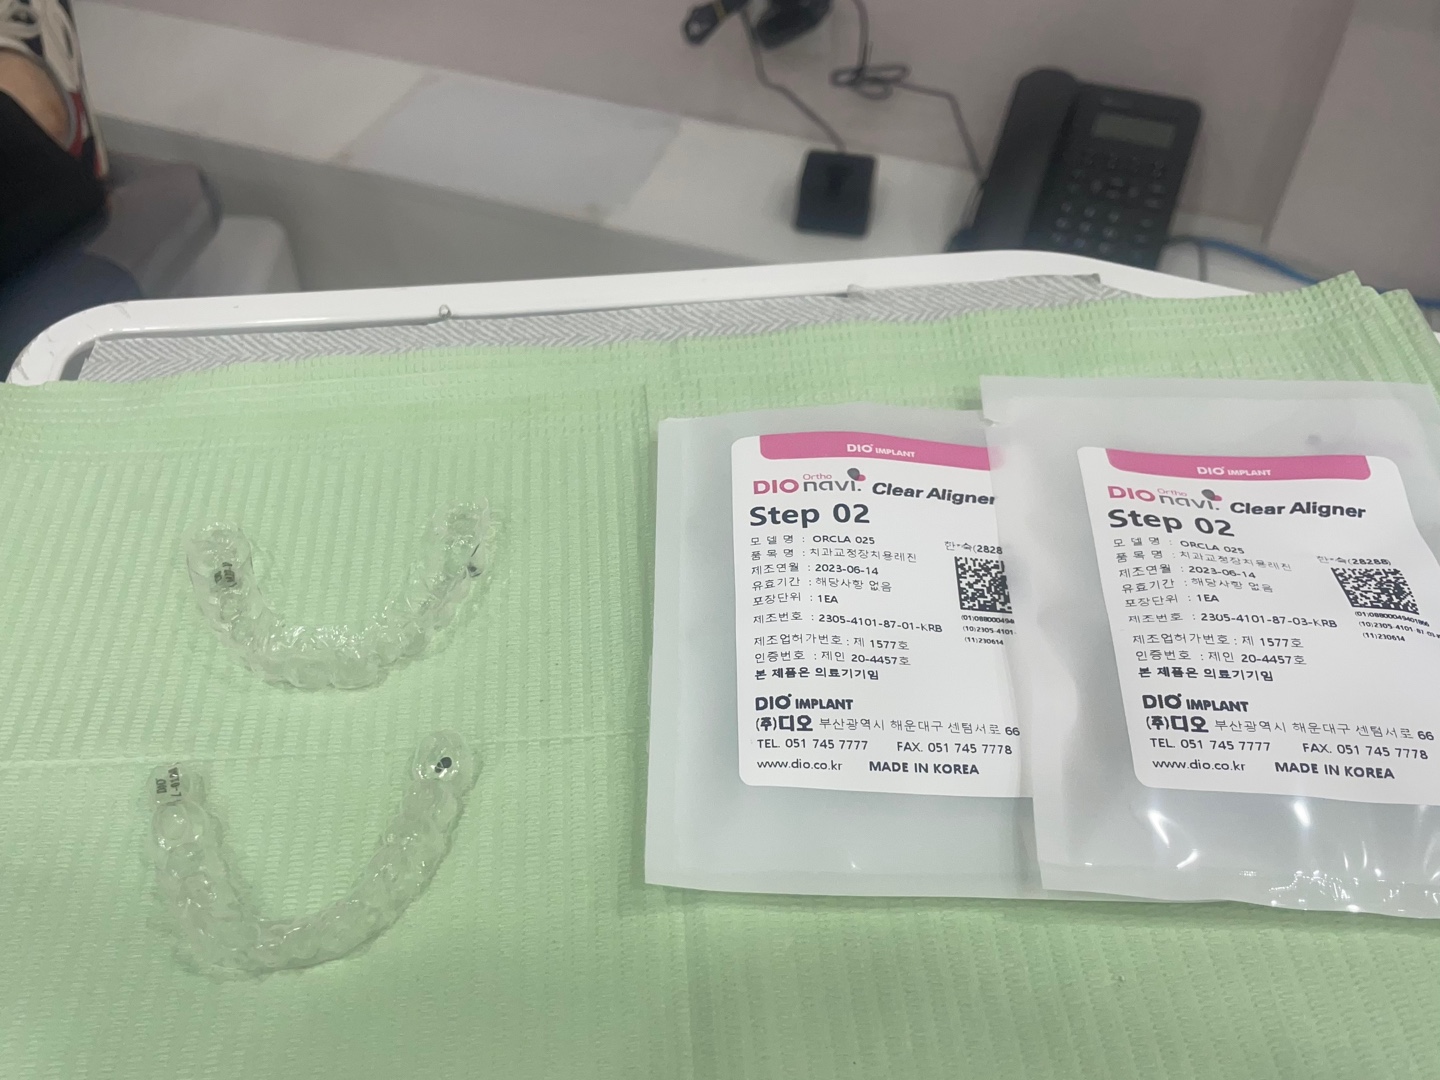

아래는 도착한 장치물입니다.